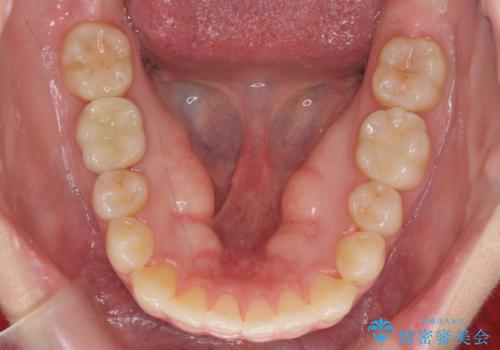

- 前歯のがたつきをきにされていました。

上下の前歯をやすりがけする処置(IPR)を行い、前歯の並びを出っ歯にしないようにしながら整えました。

症状が軽度であるためモニター採用になりました。